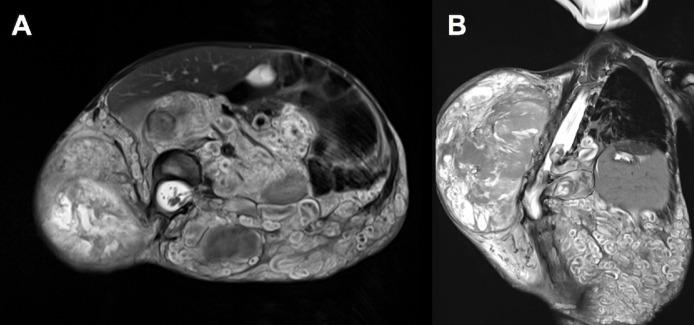

Malignant peripheral nerve sheath tumors (MPNSTs) are rare but aggressive neoplasms associated with neurofibromatosis type 1. Specifically, children with deep plexiform neurofibromas are 18 times more likely to develop MPNSTs compared to the general population. However, there is currently no standard surveillance imaging protocol for children diagnosed with deep plexiform neurofibromatosis. We present a case of a boy with neurofibromatosis type 1 and scoliosis, who later developed MPNST. This case highlights the need for more frequent surveillance imaging and the challenges of diagnosing MPNST in a patient with scoliosis. In order to facilitate early detection of malignant transformation, we suggest annual surveillance MR imaging for patients known to have deep plexiform neurofibromatosis.

摘要

恶性外周神经鞘瘤(MPNSTs)虽罕见但具有侵袭性,与1型神经纤维瘤病相关。具体而言,患有深部丛状神经纤维瘤的儿童发生MPNSTs的可能性是普通人群的18倍。然而,目前对于诊断为深部丛状神经纤维瘤病的儿童尚无标准的监测成像方案。我们报告一例患有1型神经纤维瘤病和脊柱侧弯的男孩,其后来发展为MPNST。该病例凸显了更频繁进行监测成像的必要性以及在脊柱侧弯患者中诊断MPNST的挑战。为便于早期发现恶性转化,我们建议对已知患有深部丛状神经纤维瘤病的患者每年进行监测性磁共振成像检查。